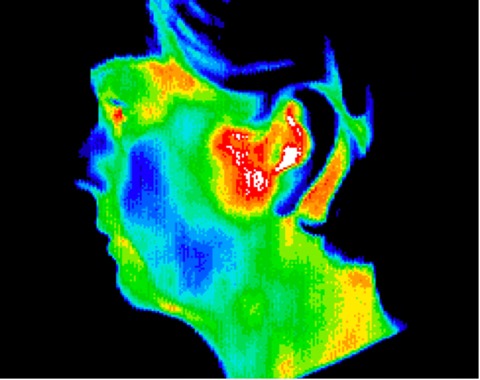

Temporomandibular joint disorder